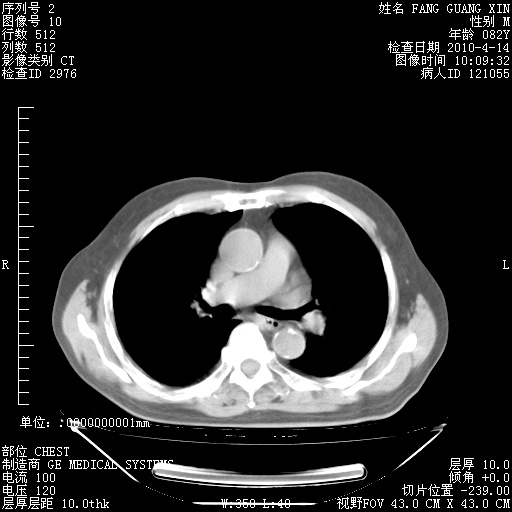

4月14日肺部CT

肺部CT平扫未见异常。

4月28日肺部CT——再次出现类似去年5月9日——透光度降低,(影像科认为)“间质性”改变。

4月28日肺部CT——再次出现类似去年5月9日——透光度降低,“间质性”改变。